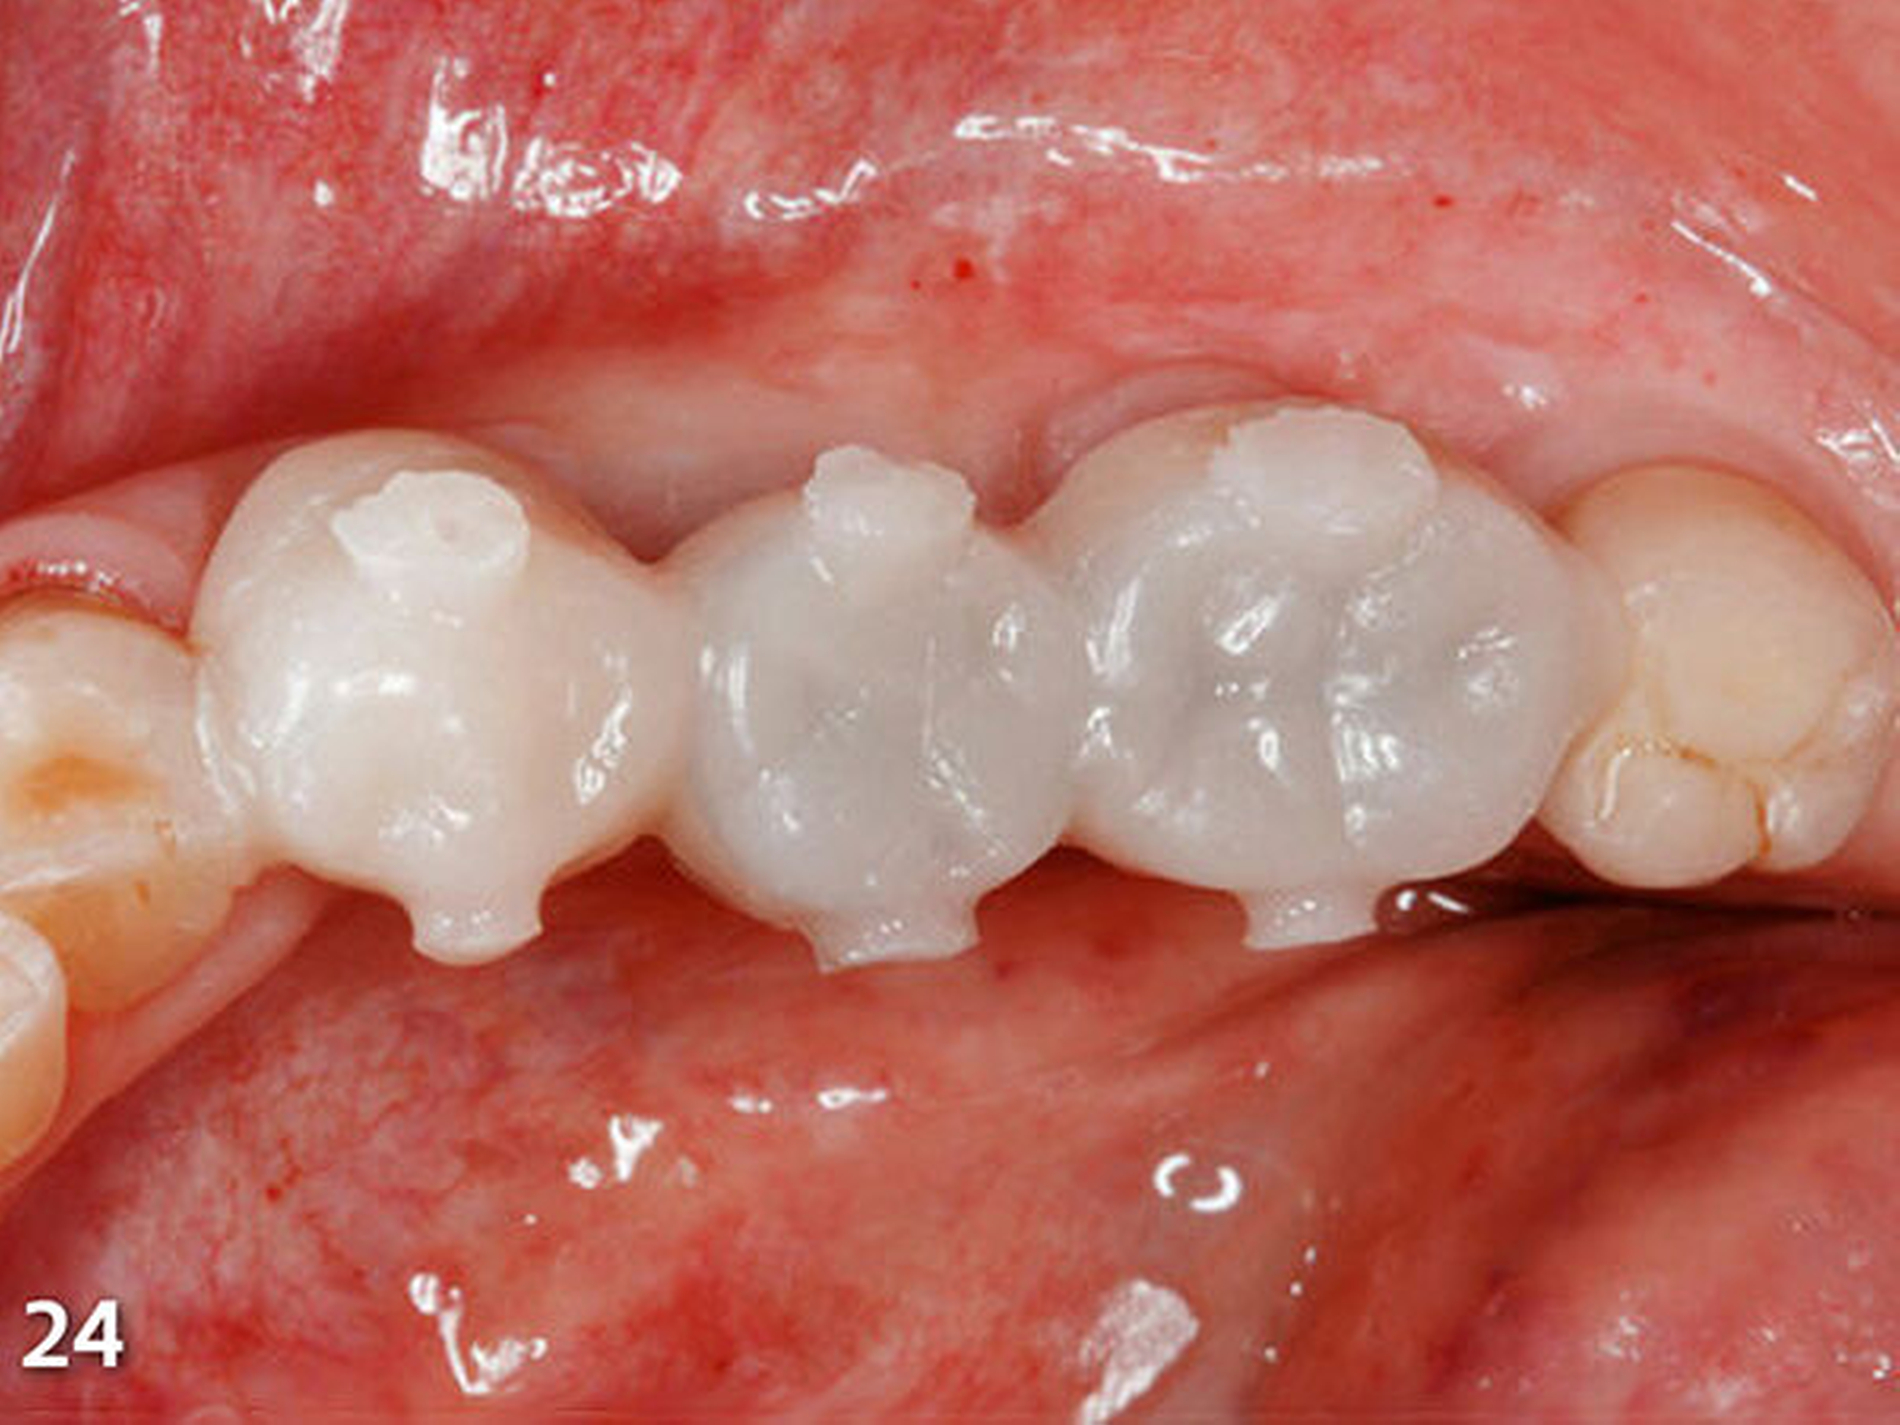

Dieser Vorgang entspricht dem in der Industrie weitverbreiteten Spritzgussverfahren in der Kunststoffverarbeitung, in dem ein plastifizierter Werkstoff unter Druck in eine formgebende Urform (Hohlraum) eingespritzt wird und nach Abkühlung oder durch eine Vernetzungsreaktion wieder den festen Zustand einnimmt (Hornbogen et al. 2012). Durch die hohe Wärmekapazität der Restaurationen bzw. Zähne, die relativ geringe Menge erwärmten Kompositmaterials und die Möglichkeit der schnellen zusätzlichen Wärmeableitung in die Mundhöhle besteht bei Anwendung dieser Technik im Regelfall keine Gefahr einer thermischen Pulpaschädigung der betroffenen Zähne. Dieses Vorgehen sollte natürlich bei Zähnen mit pulpa-nahen Kavitätenanteilen modifiziert werden, indem diese Bereiche zuerst mit einer konventionell applizierten Kompositschicht abgedeckt werden. Nach der Aushärtung des ersten aufgebauten Kauflächenbereichs mit einer leistungsstarken Polymerisationslampe wurde die Übertragungsschiene mit einem Skalpell geschlitzt und abgenommen. Es resultierte eine perfekte Übertragung der anatomischen Strukturen des Wax-up in das intraorale Okklusalsegment aus Komposit (Abb.24).

Nach dem bündigen Verschleifen der bukkalen und oralen Einspritz- und Entlüftungskanäle wurde die zweite Übertragungsschiene (Schiene 2), die ebenfalls im Frontbereich geteilt wurde, eingebracht, nachdem der damit zu rekonstruierende endständige Molar zuvor silikatisiert, silanisiert und mit Adhäsiv vorbehandelt worden war (Abb.25). Die Abstützung dieser Schablone erfolgte an den gerade zuvor im ersten Schritt aufgebauten, anterior liegenden Seitenzähnen. Der Aufbau der Kaufläche wurde wieder nach der zuvor beschriebenen Methode ausgeführt (Abb.26).